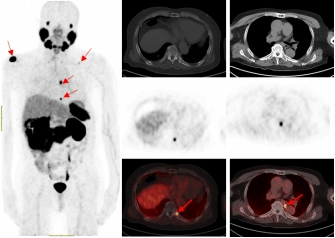

PSMA-PET/CT利用靶向核素分子影像优势,可识别最大直径为4毫米甚至更小的转移淋巴结,68Ga标记的PSMA-PET/CT诊断骨转移灶敏感性更高,能比传统检查手段早一步发现转移灶,为患者的精准治疗赢得时间。

一名75的岁男性患者自2019年确诊前列腺癌后,先后接受过两次内分泌治疗及前列腺癌根治术的综合治疗。在术后两年的复查中发现血PSA持续升高,CT检查和全身骨显像检查均未发现明显异常,医生建议随诊,患者来到PA视讯附属医院要求进一步检查。经核医学科68Ga-PSMA PET/CT检查后结果显示,双侧肩胛骨、左侧第9后肋、第2腰椎及纵隔淋巴结均已存在癌症转移。